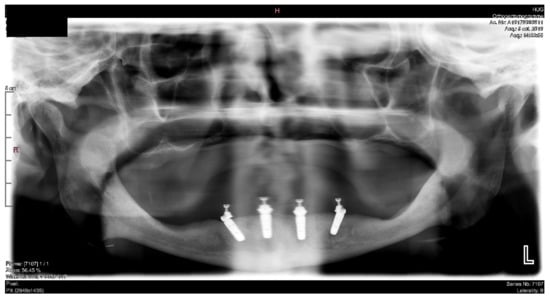

6.2.4. Intra-Operative Documentation:

In March 2013, twelve guided dental implants were placed at sites # 12, # 13, # 15, # 22, # 23, # 25, # 33, # 34, # 36, # 43, # 44, and # 46 (Figure 22, Figure 23, Figure 24, Figure 25 and Figure 26)

A screw-retained provisional fixed prosthesis was used for 4 months to condition peri-implant mucosa, and in October 2013, the final prosthesis was installed. The occlusion was adjusted, and the patient received instruction for oral hygiene. A follow-up assessment at 8 years showed a stable cosmetic, biological and functional reconstruction (Figure 27, Figure 28 and Figure 29).

Figure 29.

Panoramic radiograph showing the dental implants in place.